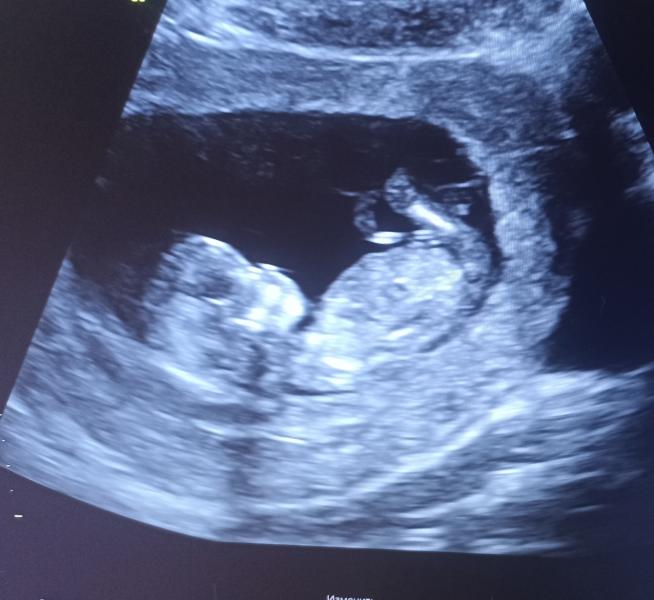

Наконец наступила дата скрининга и он пройден. Акушерский срок 12н6д, по УЗИ 13н1д, КТР 70 мм. Всё хорошо визуализируется и размеры в норме! Врач предположила девочку, сама бы я даже не подумала спрашивать, главное что всё в норме и здоровенький малыш. Гематомы мои ушли, дюфастон принимать перестала 4 дня назад.

Тоже сегодня проходила скрининг, тоже КТР 70 мм и срок 13.1😀Вот только про пол когда я спросила мне сказали не говорим до 20 недель, а я так надеялась что скажет)) Вас поздравляю!